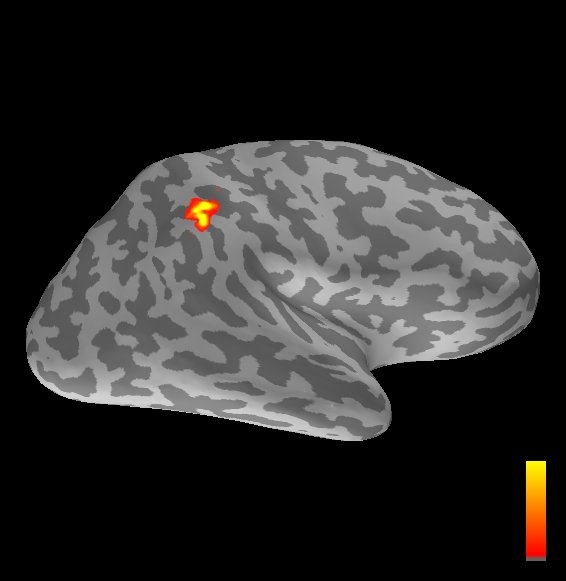

5.2 Results

We applied the ASMC sampler to MEG topographies taken from the above recordings by selecting specific time points according to the previous analysis; the parameter values in the algorithm were the same as those used for the analysis of synthetic data, with the only exception of the noise standard deviation , here estimated from the pre–stimulus interval. In order to validate the results of the ASMC, we also computed source estimates using three other methods: a PF, that approximates the posterior distribution for the current dipoles conditioned on the data up to the selected time point; dSPM, which is based on a distributed source model with an –prior, and consists in normalizing the Tikhonov regularized solution by the noise standard deviation; and sLORETA, which is similar to dSPM but is claimed to have a smaller localization bias. Figure 4 shows the results at , and ms after the stimulus onset. The results are visualized on a computer representation of the brain obtained by “inflating” the cortical surface: gray levels contain the anatomical information, light gray representing gyri and dark gray representing sulci; the activity estimate is coded in color scale, increasing from red to yellow. Importantly, this visualization allows activity in the sulci to be clearly visible; on the other hand, since neighbouring volumes may be moved apart by the inflation process, distinct activity regions are often due to underlying volumetric masses that are very close to each other.

Before describing the results, let us comment on the qualitative difference between the images produced by the ASMC sampler and the PF, on the one hand, and those produced by dSPM and sLORETA, on the other. First of all, we point out that all the quantities shown in the images of Fig. 4 are somehow related to the probability of activation at specific locations. Indeed, for both the ASMC and the PF we plot the approximation of the intensity measure (3.8); for any single grid point, this value can be interpreted as the probability of a dipole being at that location, while it integrates, over a given volume , to the mean number of dipoles within . As for dSPM, the represented quantity is a statistical value that is –distributed under the null–hypothesis of zero activity; as a direct consequence, it also yields a probability of activation, which is however not constrained to be dipolar. Similar considerations apply to sLORETA, although with a different statistical distribution. Importantly, the representation of the results is clearly affected by the setting of the visualization threshold. Owing to the explained differences between the methods, it seems reasonable to use a different value for each method. At the same time, since the plotted quantity is a probability of activation, it seems right to use the same thresholding for different time points. In this connection, the thresholds in Fig. 4 have been chosen by hand following the guidelines just outlined.

Using the same thresholding and parameters at different time points makes the four methods respond differently to the diverse intensities of the different sources. Whenever a stronger source is active, both sLORETA and dSPM will tend to produce widespread estimates, while weaker sources will be represented as small active areas. The behaviour of the ASMC and of the PF is the opposite: a stronger signal will lead to a precise localization of a dipolar source, and then to a focal marginal distribution for the location; a weaker signal will translate to higher uncertainty on the source position, and therefore a more widespread posterior map.

The phenomenon just described is indeed clearly visible in Figure 4. At ms, all the methods correctly identify the rather strong activation in the contra–lateral primary somatosensory cortex: the ASMC and the PF provide very focal maps, while dSPM and sLORETA provide compatible widespread estimates; dSPM also exhibits a more posterior peak which does not fit with the commonly agreed models of the response to median nerve stimulation; this may be due to the formerly described brain inflation.